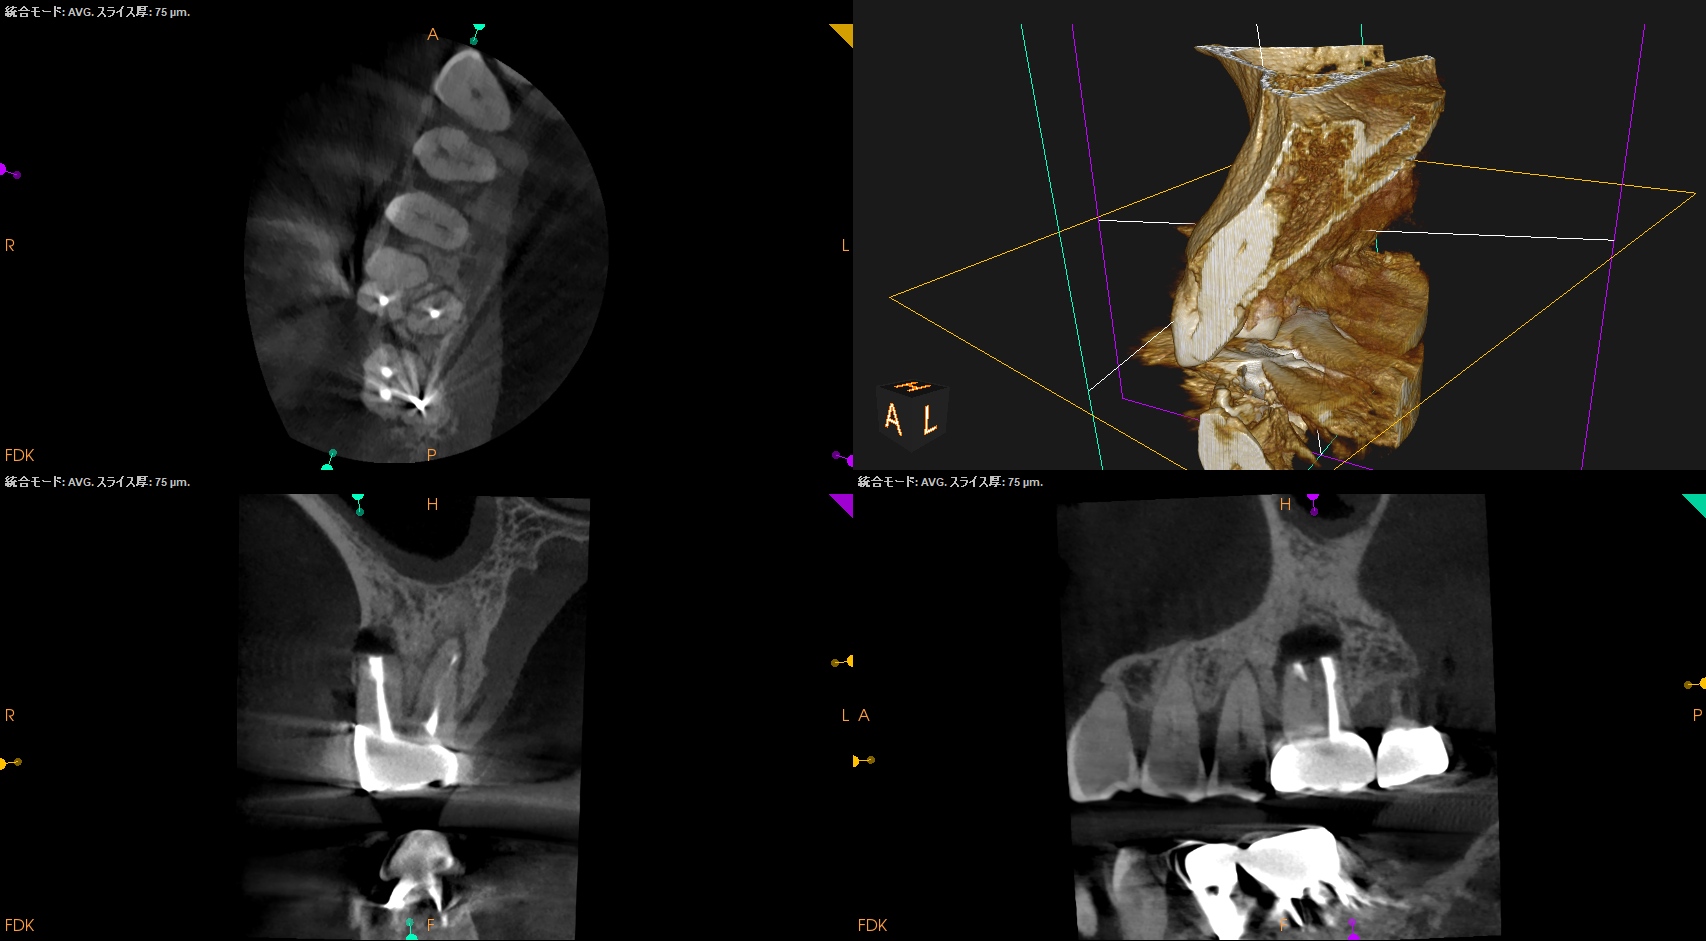

Pre-op CBCT(2024.11.25)

MB

DB

P

B

P根以外のMB,DBには根尖病変がありSinus tractがある。

ということは…

MB+DB Apicoectomyだ。